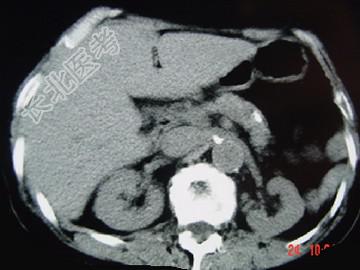

- 单项选择题女,54岁, 中上腹痛,体重减轻, 消化不良,脂肪痢、便量多、泡沫状。影像检查如下图, 最佳诊断是 ( )

B、慢性胰腺炎